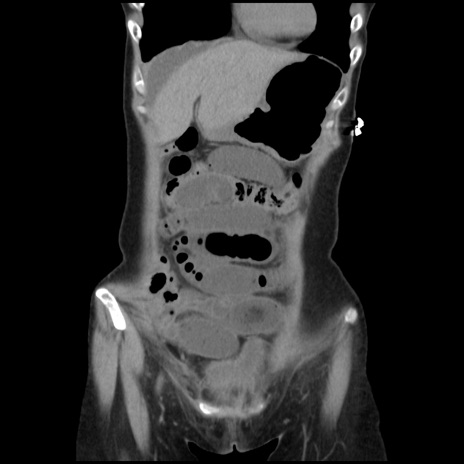

症例32(冠状断像)

【症例】40歳代 女性

【主訴】上腹部痛、嘔気・嘔吐

【現病歴】約9時間前頃から急に上腹部痛、嘔気、嘔吐が出現。改善しないため救急要請。

【既往歴】子宮頚癌(広汎子宮全摘術、放射線療法)、腸閉塞

【身体所見】腹部:平坦、軟、腸雑音亢進、上腹部を中心に腹部全体に圧痛あり。

【データ】WBC 8400、CRP 0.03